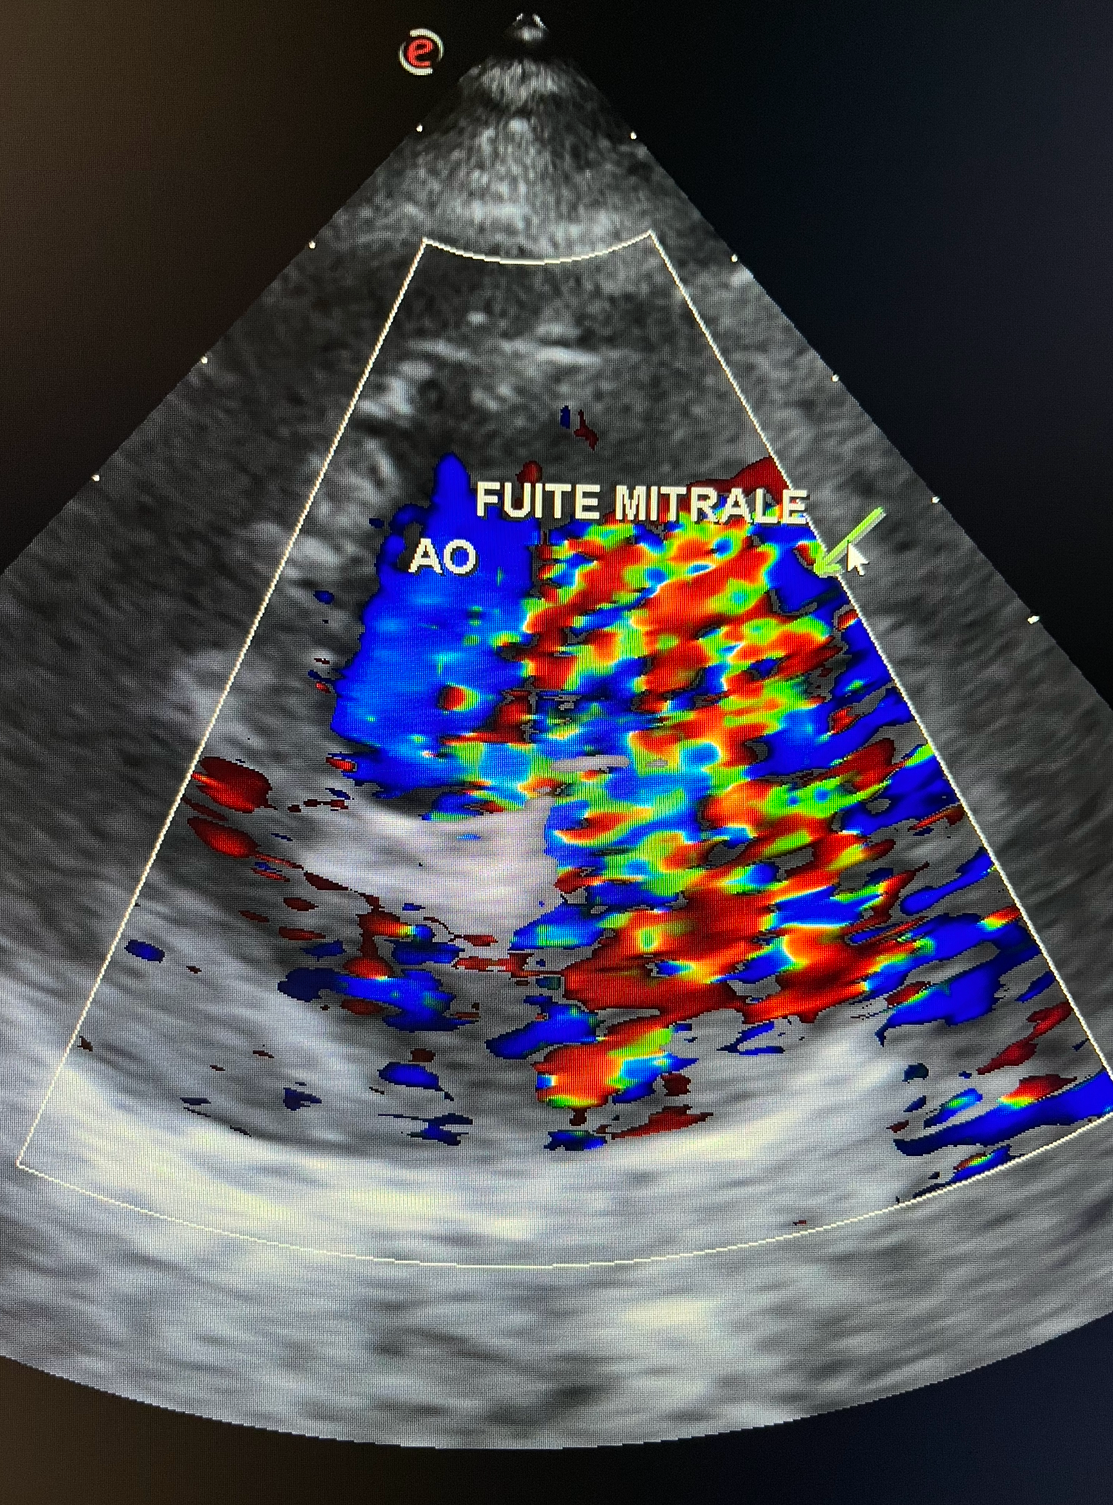

Échographie Cardiaque

Les échographies thoraciques permettent quand à elle d’étudier et de suivre l’évolution des pathologies cardiaques mais également d’observer des épanchements ou des tumeurs thoraciques.